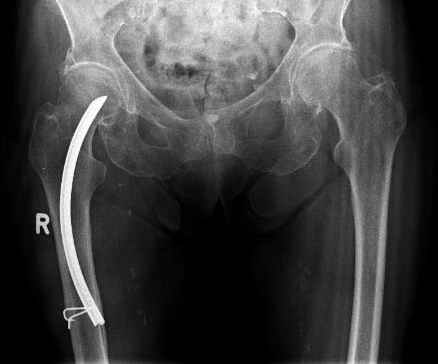

Поступила пациентка 75 лет с пертрохантерным переломом левой бедренной кости. 15 лет назад перелом справа, который прооперировали тогда гвоздем лециуса.

Я его только в книжках видел. Сейчас остеосинтез гамма-нагелем справа. Пациентка стала примером прогресса медицины. Век живи, век учись...Вальдемар Киндсватер.